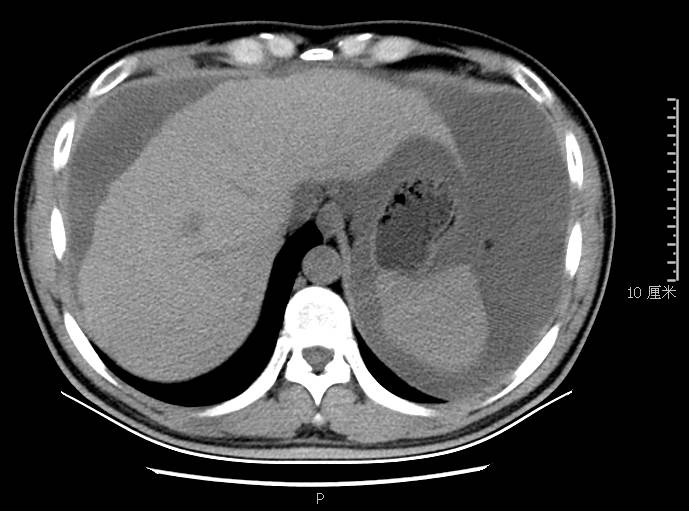

全腹CT:(1)结合病史考虑腹膜炎(见图2A),大量腹水;(2)右骼窝区管状样结构,考虑阑尾扩张(见图2B);(3)肝脏多发小囊肿(见图2C);(4)肝内胆管轻度扩张,建议隔期复查。

图2a大网膜成饼状(CT腹腔横断图象上出现肠曲被前面及两侧的肿瘤组织限制在中央

本例确诊后对B超及CT再次回顾发现:腹腔、盆腔可见不均质中强回声包块,部分呈囊实状,腹膜增厚,大网膜成饼状(如图2A)和肝周可见不均质中强回声弧形压迹、脾周可见不均质中强回声包饶,肝脏成扇贝样改变(如图2C),但在诊断报告中未提及。有学者发现mantle和scalloping(如图2A,2C)在PMP中具有代表性,且mantle较scalloping更为常见,若mantel征同时伴有大小不一的囊性改变,则更具诊断价值。

图2c肝脏成扇贝样改变(肝脏由于受肿瘤实质性或囊性组织压迫而其实质却未受侵犯,于是在一处或多处呈下凹状或扇形皱褶状(scalloping)